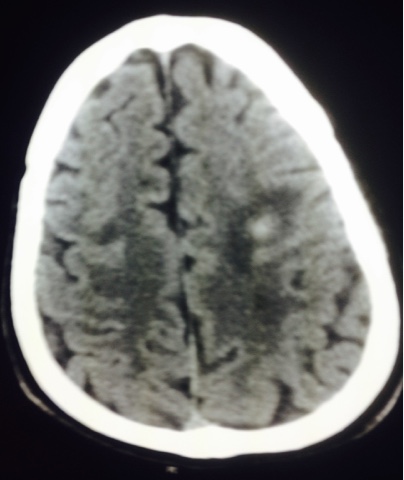

CT scan head revealed 15 mm hypodense lesion left high frontoparietal region with ring enhancement suggestive of the cerebral abscess. There were other multiple abscesses seen in the right occipital lobe . Fig 2 There was no midline shift and the ventricular system was normal. The findings were confirmed by MRI brain.

Fig 2 CT scan showing infarct Fronto parietal region